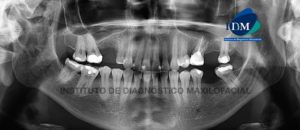

Paciente femenino de 51 años de edad, es referido al Instituto de Diagnóstico Maxilofacial – IDM para evaluación general. En la reformación panorámica de la